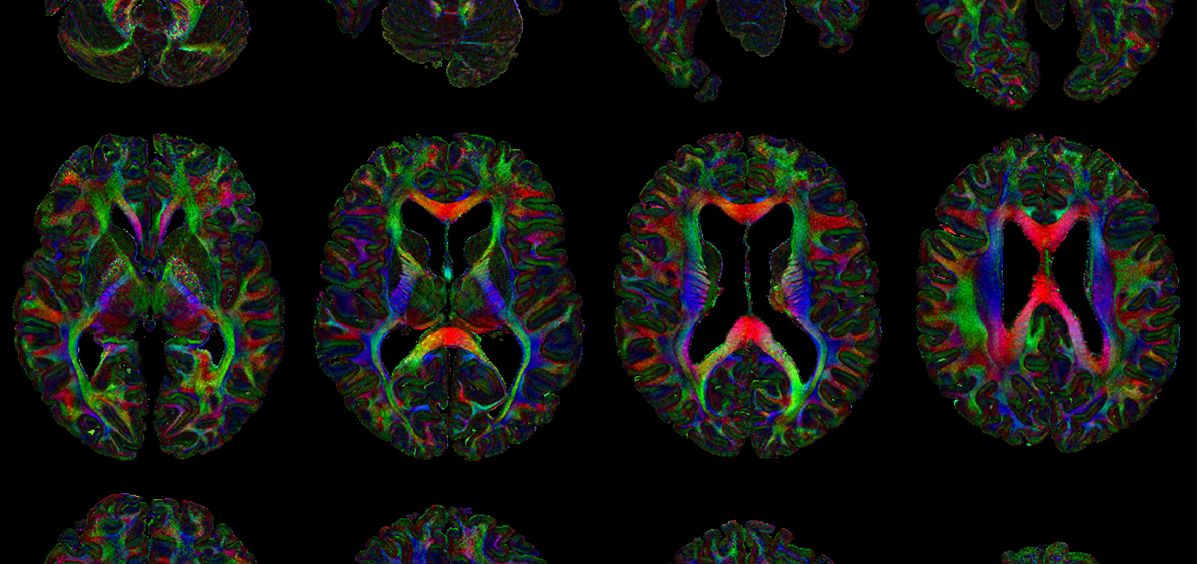

Los muertos no solo dan información sobre la constitución del cuerpo humano, sino también sobre la forma de desarrollarse las enfermedades, de evolucionar y dañar el cuerpo, una idea que ya el griego y padre de la medicina, Claudio Galeno, defendía a capa y espada, y que la que en la actualidad es base de muchas de las estrategias con las que conseguir curas. Y la evolución en las nuevas tecnologías y por ejemplo en la neuroimagen permiten ahora conseguir imágenes cerebrales post-mortem de alta resolución realizadas con resonancia magnética sin necesidad de abrir los cuerpos.

Durante una década la Universidad de Oxford ha investigado la resonancia magnética post-mortem obteniendo imágenes de alta calidad de las personas sanas y enfermas fallecidas y nuevas técnicas para mejorar los resultados de las neuroimágenes. Todo ello se ha publicado en una plataforma, Digital Brain Bank, de acceso abierto y gratuito que se irá ampliando.

El banco, al que se puede acceder aquí, ha sido creado por un equipo internacional y multidisciplinar y recoge 21 conjuntos de datos distintivos de resonancia magnética de difusión de todo el cerebro para investigaciones de conectividad estructural, junto con microscopía y modalidades complementarias de resonancia magnética. Se trata del primero de los conjuntos de datos de resonancia magnética con una resolución “jamás adquirida”, señalan en la investigación publicada en la revista eLife.

La plataforma cuenta con conjuntos de datos para investigaciones neuroatómicas para facilitar el examen del cerebro humano. Entre el conjunto de datos recogidos se encuentra una resonancia magnética, una imagen de luz polarizada y una histología de un cuerpo calloso, o una imagen de resonancia magnética de difusión post-mortem humana de un cerebro completo, junto con dos modalidades de resonancia magnética complementaria e imágenes de luz polarizada regional. El banco a su vez cuenta con un apartado con datos que facilitan el examen de la neuropatología humana y los correlatos de la patología de resonancia magnética con el ejemplo de una resonancia magnética postmorten de un cerebro de un paciente con esclerosis lateral amiotrófica (ELA)